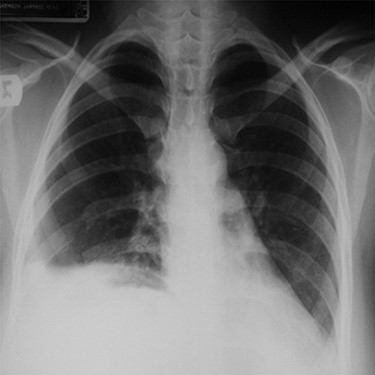

Chest x-ray (on arrival) showing a homogeneous opacity (the liver) occupying the right hemi-thorax with some bowel loops the right hemi-thorax with obvious mediastinal shift to the left side.

Upon arrival, she was in respiratory distress with tachypnea (RR: 25/min) and tachycardia (116/min), but normal blood pressure (130/80). Chest examination revealed diminished air entry and dull percussion on the right side. Abdominal examination was unremarkable.

Her routine laboratory investigations including white cell count were normal. Electrocardiogram showed sinus tachycardia. Chest x-ray showed homogeneous opacity occupying the right hemi-thorax, and bowel loops were seen above the right chest with obvious mediastinal shift to the left side (Fig. 1). Abdominal computed tomography (CT) scan with contrast